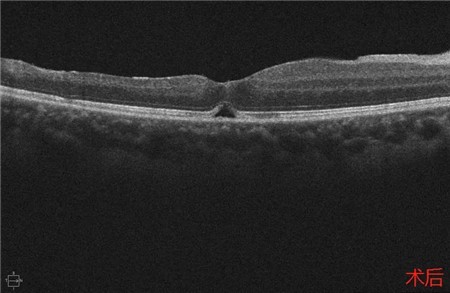

经过详细的眼底检查后,患者被诊断为IRVAN综合征引起的右眼黄斑裂孔,张风院长带领医生团队为患者施局右眼玻璃体切除+剥膜+眼内光凝+气液交换手术,经过半个月的恢复,患者右眼术后视力由术前0.3-达到0.6-的状态,且裂孔呈逐渐闭合状态。